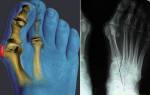

Профилактика и комплексное лечение различных типов остеопороза;

- Лечение переломов костей.